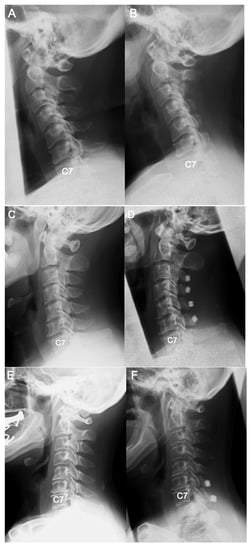

Differences in Demographic and Radiographic Characteristics between Patients with Visible and Invisible T1 Slopes on Lateral Cervical Radiographic Images

- Park, B.J.; Gold, C.J.; Woodroffe, R.W.; Yamaguchi, S. What is the most accurate substitute for an invisible T1 slope in cervical radiographs? A comparative study of a novel method with previously reported substitutes. J. Neurosurg. Spine 2021, 1, 1–7. [Google Scholar] [CrossRef] [PubMed]

- Tamai, K.; Buser, Z.; Paholpak, P.; Sessumpun, K.; Nakamura, H.; Wang, J.C. Can C7 Slope Substitute the T1 slope?: An Analysis Using Cervical Radiographs and Kinematic MRIs. Spine 2018, 43, 520–525. [Google Scholar] [CrossRef]

| T1 slope visibility (V group/I group) | 53.3% (32/28) | 33.3% (10/20) | 73.3% (22/8) | <0.05 |

| Male:Female | 30:30 | 10:22 | 20:8 | <0.05 |